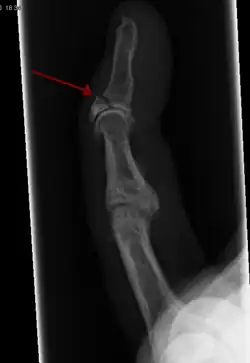

Internal and external views of an arm with a compound fracture, both before and after surgery | |